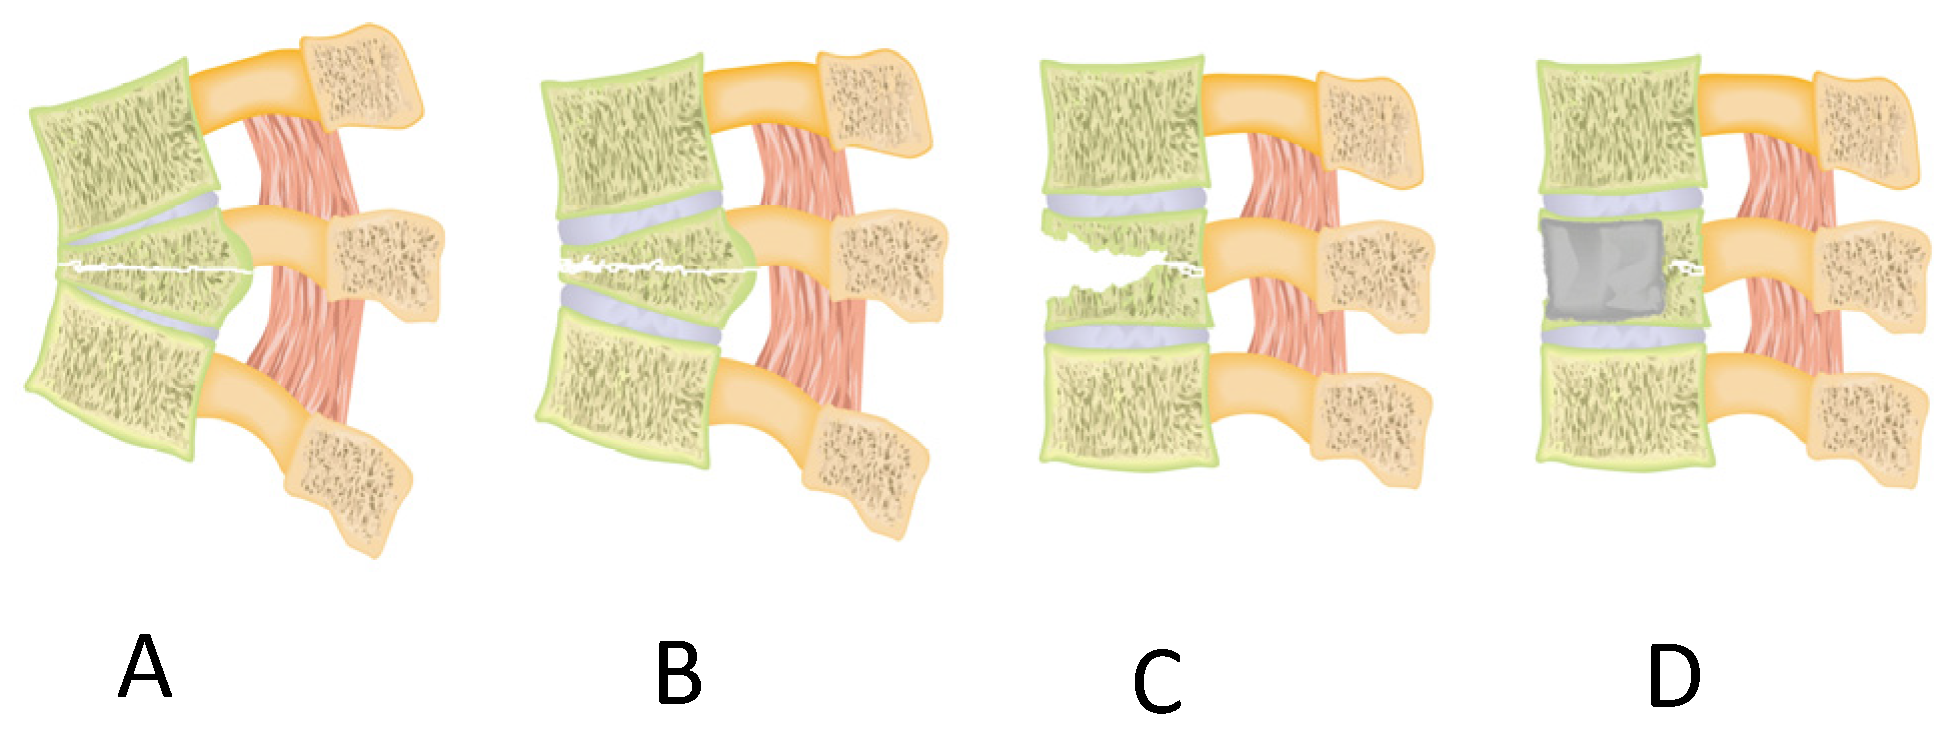

2. Materials and Methods

4. Discussion